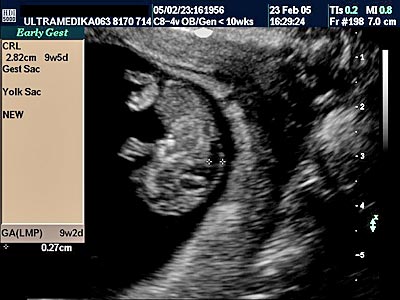

A) Prvi marker za hromozomsku anomaliju (najčešće se misli na trizomiju 21 para hromozoma) je neadekvatna veličina Yolk sac-a (žumančane kese) u 7 nedelji gestacije (GN).

B) Drugi marker je registrovanje postojanje povećane debljine prozračne zone (NT) u vratu ploda-embriona. Obično greške nastaju kada se kontura vrata ploda ne razlikuje od amniona - opne u kojoj se plod nalazi. Osim znanja doktora, rezolucija slike Ultrazvučnog aparata čini ključnu ulogu u merenju ove strukture. Ona-NT se meri u periodu od 9 do 14 GN. Iako je najveća normalna debljina NT 2,5 mm na kraju 14 GN ova vrednost NT može ukazivati na trizomiju ako je registrovana na početku ovog vremenskog perioda. Samo Ultrazvučna kompjuterizovana tomografija može u velikom procentu pouzdano izmeriti ovu strukturu i to na dva načina. Pregled endovaginalnom sondom Braund-band od 8-4MHz, često zbog pozicije ploda nije u stanje da adekvatno registruje NT. Pregled se može znatno zbog toga produžiti i ne mora tačno izmeriti debljinu NT. Međutim u ovakvim situacijama upotrebom Braund-band sondi koje koriste ceo opseg ultrazvučnih talasa od 12 do 5 MHz, pregled se u velikom broju slučajeva završava pregledom preko prednjeg trbušnog zida. Ovaj transabdominalni pregled ima prednosti zbog mogućnosti boljeg pozicioniranja ultrazvučne sonde

u odnosu na položaj ploda, pri čemu je kvalitet slike neuporedivo bolji u odnosu na pregled vaginalnom sondom. Jedino konstitucija trudnice donekle ograničava pregled preko prednjeg trbušnog zida (mokraćna bešika ne mora biti puna).